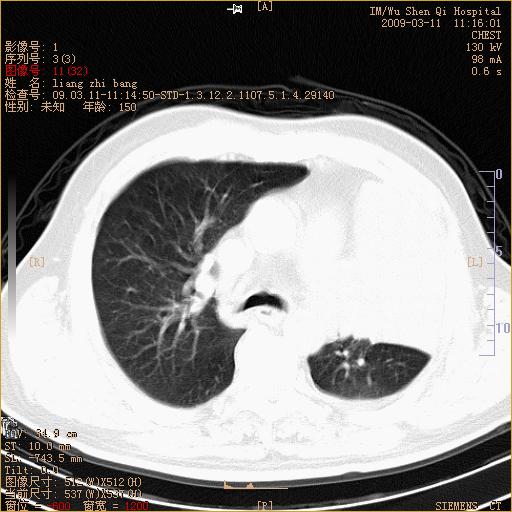

标题: CT18604:男,60岁,咳嗽一月余 [打印本页]

标题: CT18604:男,60岁,咳嗽一月余

1)考虑左肺上叶中央型肺癌并左肺上叶肺不张;建议必要时行纤支镜检查进一步明确诊断。2)左侧胸腔积液。

肺门肿块、支气管开口闭塞伴肺不张及胸水!典型的中心型肺癌变现!

1、左肺上叶中央型肺癌并上叶阻塞性肺不张。

2、左侧胸腔少量积液,右侧胸膜轻度增厚。

左肺们肿块并左肺上叶不张。考虑左肺中心性肺癌并左肺上叶不张及左侧胸腔积液